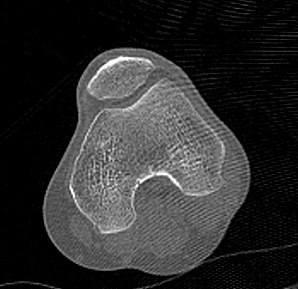

Одним из наиболее информативных методов исследования коленных суставов является мультиспиральная компьютерная томография. КТ относится к лучевым методам исследования и основана на применении ионизирующего излучения с последующей цифровой обработкой данных, полученных при КТ-сканировании.

В наших медицинских центрах обследование коленного сустава проводится на современных мультиспиральных компьютерных томографах последнего поколения TOSHIBA AQUILION. При помощи рентгеновских лучей аппараты послойно сканируют в разных плоскостях исследуемую область с толщиной среза от 0,5 мм. В результате получаются детальные снимки и цифровые трехмерные изображения коленного сустава в мельчайших подробностях. Помимо точности и достоверности диагностики современные компьютерные томографы обеспечивают для пациента минимальную дозу рентгеновского облучения.

Мультиспиральная компьютерная томография дает возможность оценить структуру костной ткани, выявить переломы, воспалительные изменения, участки деструкции костей и диагностировать опухолевые образования. Мультиспиральная КТ часто применяется в ортопедии и травматологии. За счет быстроты, доступности и неинвазивности (то есть обследование выполняется без вмешательства в организм) метод незаменим при травмах сустава, а также при планировании оперативных вмешательств, например, в случае эндопротезирования сустава. В послеоперационном периоде КТ помогает оценить эффективность проведенной операции, вовремя выявить осложнения и отследить процесс восстановления.

Что показывает КТ коленного сустава

- переломы костей;

- артроз;

- артрит;

- скопление жидкости в суставе;

- кисту Бейкера;

- костные наросты на поверхности сустава;

- новообразования

- полные или неполные вывихи — по смещению образующих сустав элементов относительно друг друга;

- деформирующий остеоартроз, ревматический полиартрит

- злокачественную или доброкачественную опухоль

- гемартроз

- абсцесс.